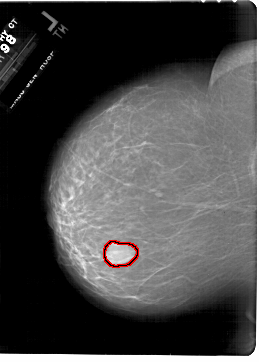

A_1801_1.LEFT_MLO

FILE: A_1801_1.LEFT_MLO.OVERLAY

TOTAL_ABNORMALITIES 1

ABNORMALITY 1

LESION_TYPE MASS SHAPE LOBULATED MARGINS CIRCUMSCRIBED

ASSESSMENT 4

SUBTLETY 5

PATHOLOGY BENIGN

TOTAL_OUTLINES 1

BOUNDARY